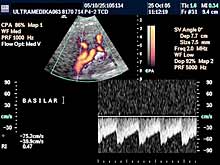

- transkranijalni kolor Doppler (TCD) i 3D CPA pregled

(otkrivanje

kritičnih stenoza, i proširenja-aneurizmi krvnih sudova mozga),

Primenjene tehnike:

- Broadband-CD,

- CPA,

- CPD,

- 3D CPD,

- Sono CT,

- XRes,

- 2D Broadband.